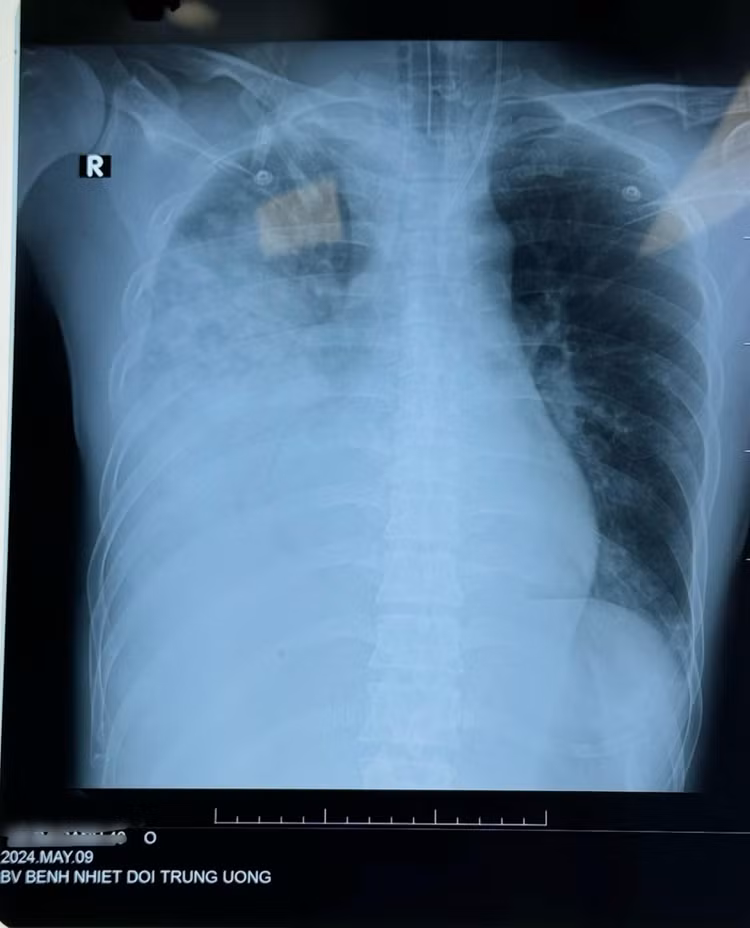

Bệnh nhân Nam, 40 tuổi ở Thanh Hóa nhập khoa Cấp cứu, Bệnh viện Bệnh Nhiệt đới Trung ương ngày 08/5/2024. Bệnh nhân có tiền sử: khỏe mạnh. Cách vào viện 5 ngày, bệnh nhân xuất hiện sốt cao, hắt hơi, sổ mũi, ăn uống kém. Khi thấy khó thở đau tức ngực sau xương ức, khó thở tăng dần, ho khạc đờm xanh bệnh nhân nhập viện được test Cúm B (+).

Khi chụp cắt lớp có hình ảnh tổn thương phổi bên phải, được chẩn đoán: Viêm phổi nặng - Cúm B. Bệnh nhân được thở O2 mask và chuyển đến Bệnh viện bệnh Nhiệt đới Trung ương. Bệnh nhân nhập trong tình trạng khó thở và tức ngực nhiều, sau đó được đặt ống thở máy. Hiện tại bệnh nhân đã được đặt ECMO.

![]() |

| Tổn thương phổi do cúm B trên phim chụp - Ảnh BVCC |